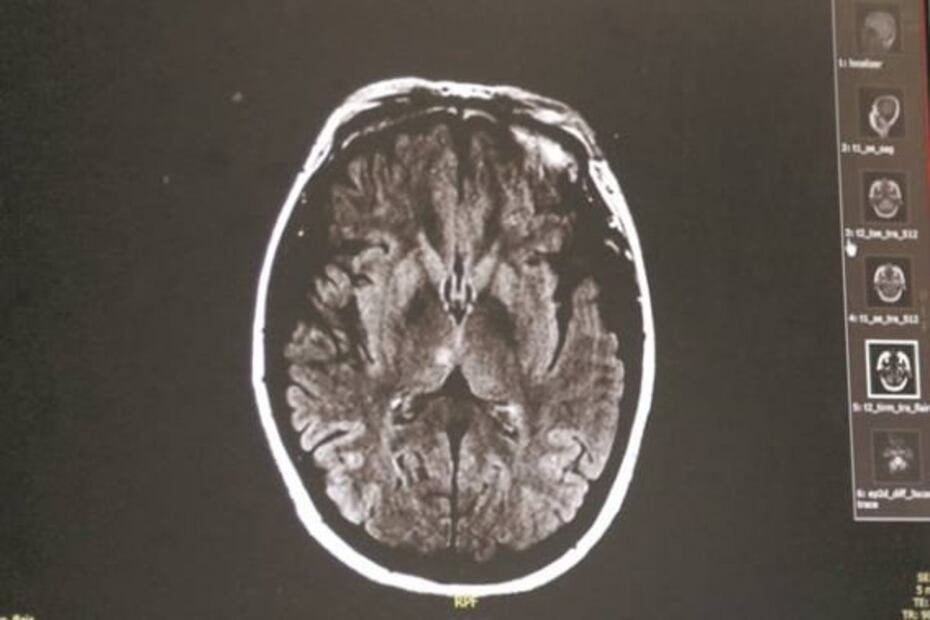

Con las tomografías se diagnostica si el paciente sufrió daños en el cerebro.

Después, los especialistas llevan a cabo una escala neurológica en patología vascular cerebral con la que valoran las funciones neurológicas básicas, una tomografía para tener imágenes del cerebro, se aplica una escala dragón, con la que se decide si el paciente es candidato para el tratamiento trombolítico.